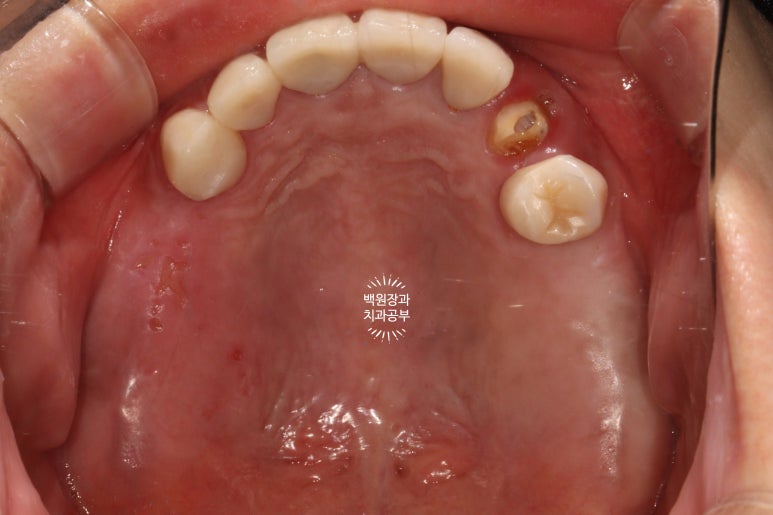

교합면에서 촬영한 것을 보면, 다수의 치야가 완성되어 드뎌 원래 치아가 있었던 상태로 돌아간 것을 보실 수 있어요.